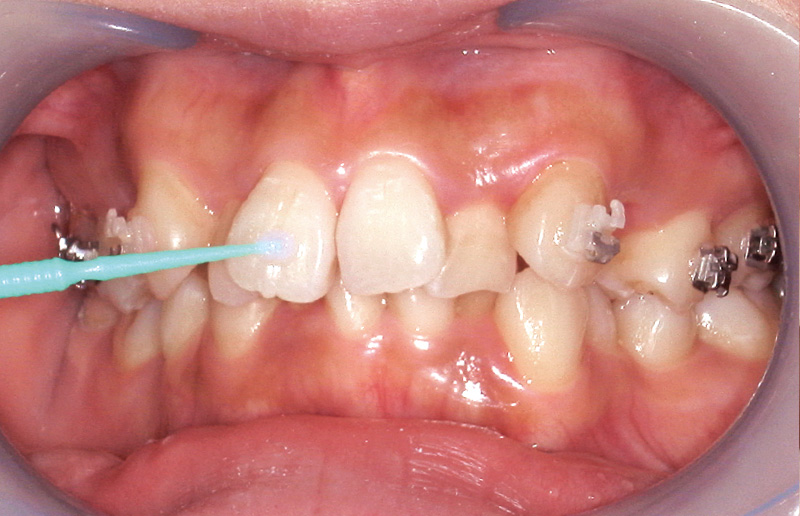

動的治療終了時のブラケット除去について考察する。矯正治療において、接着材の選択は『装置を確実に接着すること』だけでなく、『デボンド時の歯面への負担を最小限に抑えること』も重要である。筆者の臨床では、CR系矯正用接着材と4-META/MMA-TBB系レジン接着材を部位や状況に応じて使い分けている。具体的には、補綴装置へのブラケット接着、一度ブラケットが脱離した部位、大臼歯など防湿管理が難しい部位では、エッチング処理後に「ボンドフィルSBⅡ」を選択している。また、前歯部など審美的要求が高く脱離リスクが比較的低い部位に対しては、「ティースプライマー」処理後に同じく「ボンドフィルSBⅡ」を使用する。一方で、接着難易度が低い下顎前歯部やブラケットのポジショニングに時間を要する小臼歯部では、操作性に優れるCR系矯正用接着材を選択している。筆者の臨床経験から、エナメル質の歯面処理材に「ティースプライマー」を用い、「ボンドフィルSBⅡ」で接着した場合、ブラケット除去時にはレジンの多くがブラケット側に残り、歯面に残るレジン量は比較的少ない(図14A, B)。そのため、歯面に残存するレジン除去の時間を短縮でき、回転切削器具の使用を最小限に抑えることが可能となる。一方、CR系矯正用接着材を用いてブラケットを接着した場合には、デボンド時にレジンが歯面に残るため、その切削除去に多くの時間と慎重な作業を要する。また、「スーパーボンド」や「ボンドフィルSBⅡ」は熱で軟化する性質があるため、弱い圧で効率的に除去が可能であり、レジンリムービングプライヤーによる除去も容易である。

図14A, B デボンド直後のレジン残留状況比較

(上顎:「ティースプライマー」+「ボンドフィルSBⅡ」で接着。下顎:CR系光重合型矯正用接着材で接着)

A:ブラケット除去直後の口腔内写真。上顎前歯は「ティースプライマー」使用

B:下顎は光重合系レジンセメントを使用しており、ブルーライト下で発光している状態。ほとんどのレジンが歯面に残存していることがわかる。 -